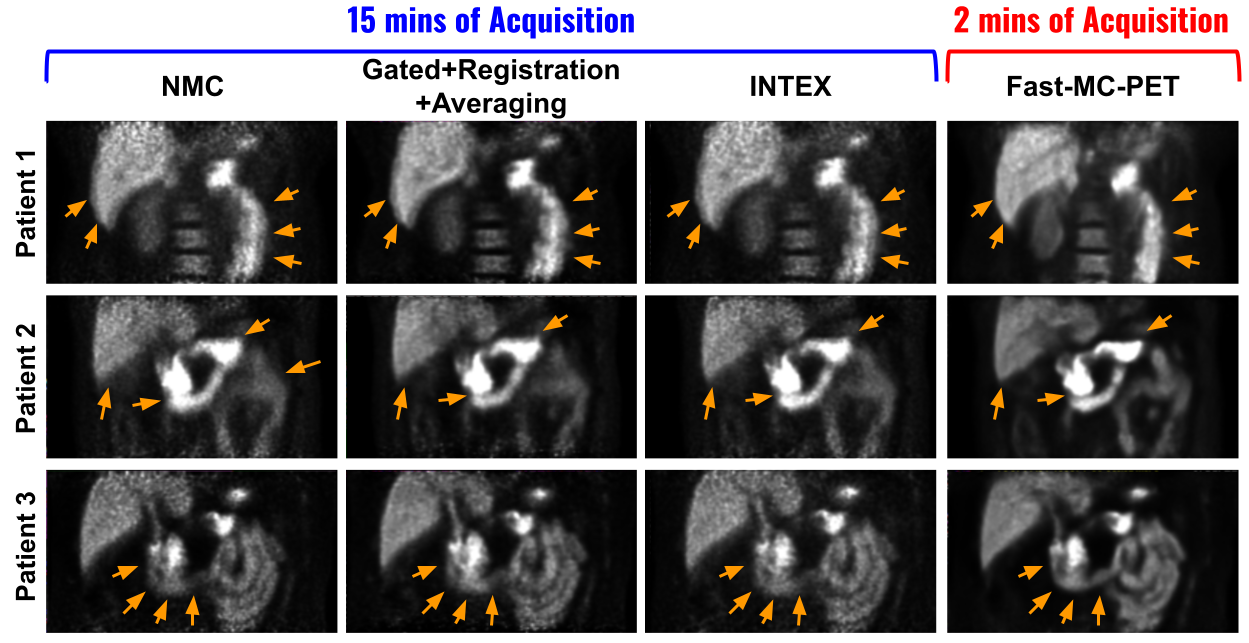

Figure 4: Comparisons to previous motion correction methods. Our Fast-MC-PET with 2 minutes acquisition show improved structural details recovery (orange arrows), as compared to previous methods with 15 minutes acquisition.

We compared our 2 minutes-based Fast-MC-PET reconstructions to previous correction methods that are long acquisition based, i.e. 15 minutes. The visual comparison is shown in Figure 4. First, we compared with the classic respiratory motion correction method [2] that reduces the motion and noise by averaging the aligned amplitude-gated images, where non-rigid registration [16] is used for alignments. Then, we compared our method with the NR-INTEX [4] that compensates for the respiratory motion by estimating the continuous deformation field using internal-external motion correlation which is considered the current state-of-the-art method. Both previous methods require specific motion-type modeling, and thus fail when additional motion types are present, e.g. body motion (Patient 1) and bowel motion (Patient 3). The UMC module in the Fast-MC-PET is not specific to any motion type and thus can correct different types of motion together. Therefore, our Fast-MC-PET can provide consistently better results when multiple types of motion co-exist (Patients 1 and 3), and generate comparable reconstruction quality when respiratory motion is dominating (Patient 2).